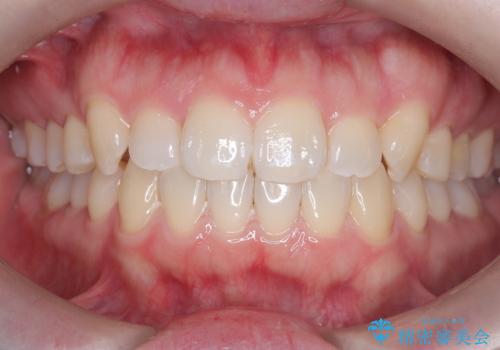

- 患者様は歯並びの乱れを気にされて来院されました。特に小臼歯の捻転(ねじれ)が強く、見た目だけでなく噛み合わせにも影響がありました。できるだけ目立たない方法を希望されていたため、インビザライン(マウスピース矯正)を基本としつつ、より精密な動きが必要な部分にはワイヤー矯正を併用する計画を立てました。また、小臼歯の捻転については**部分矯正(MTM:Minor Tooth Movement)**を取り入れ、効率的に改善を目指しました。

まず、全体の歯並びを整えるためにインビザラインを使用し、徐々に理想的な位置へと歯を移動させました。一方で、ねじれの強い小臼歯に対しては、**部分的なワイヤー矯正(MTM)**を行い、より精密なコントロールを実施。約2年の治療期間を経て、歯並びと噛み合わせが整い、見た目の美しさだけでなく、機能的な改善も達成しました。患者様からは「自然な仕上がりで、自信を持って笑えるようになった」と喜びの声をいただきました。